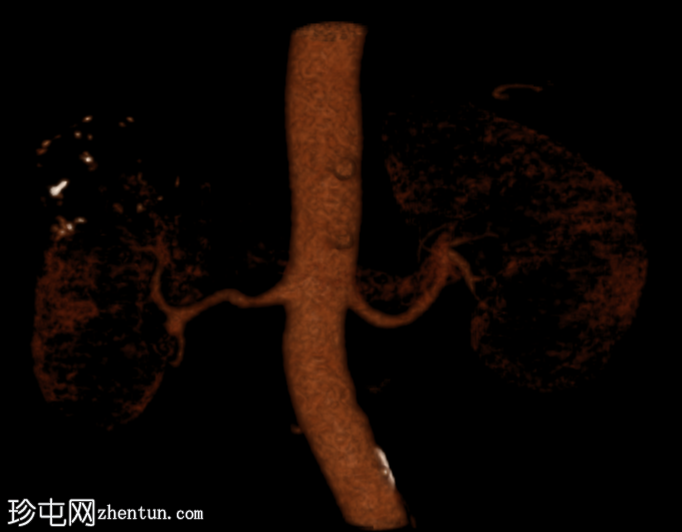

重建图像

VR三维图像

右肾上极前外侧可见一边界清晰、分叶状、部分外生性病变,大小约4.0 x 6.8 cm(轴位)。病变内侧为无强化囊性成分,直径2.3 cm(动脉期和门静脉期平均密度均为13 HU);外侧为强化实性成分,直径4.5 cm(动脉期和门静脉期平均密度分别为68 HU和78 HU)。病灶内可见多处小钙化灶。病灶毗邻肝右叶,但未见侵犯肝实质的证据。肾静脉和下腔静脉通畅。肾门水平可见数个小的主动脉腔静脉淋巴结和腔静脉后淋巴结,其中最大的腔静脉后淋巴结短轴直径为7毫米。